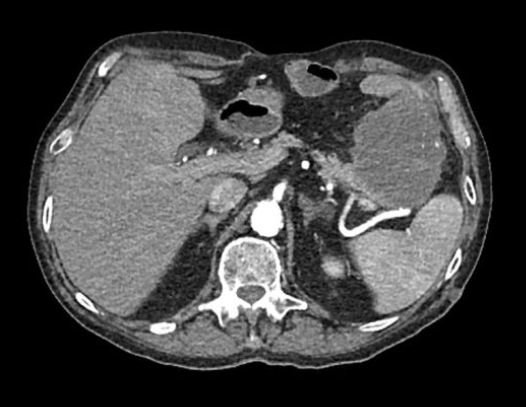

- 진단 검사: 혈액 검사(아밀라아제, 리파아제)와 복부 CT로 확진할 수 있습니다